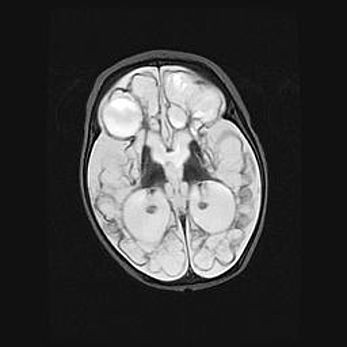

Множественные кисты обоих полушарий головного мозга, наибольшая из них в правой затылочной области. Ассиметричная атрофическая гидроцефалия.

Возраст: 7 месяцев

Вес: 5660 г

Пол: мужской

Окружность головы: 41,5 см

Срок гестации: 28-29 недель

Кисты головного мозга развиваются в результате многоочаговых некрозов вещества мозга и возникают вследствие перенесенной перинатальной инфекции, менингитов, энцефалитов, асфиксии, родовой травмы, расстройств мозгового кровообращения различного генеза. Образованию кист в веществе головного мозга плодов и новорожденных способствуют такие факторы, как высокое содержание в нем воды, недостаточная (или отсутствие) миелинизация и слабая астроглиальная реакция на повреждение.

Кисты могут сочетаться с гидроцефалией и другими поражениями головного мозга.